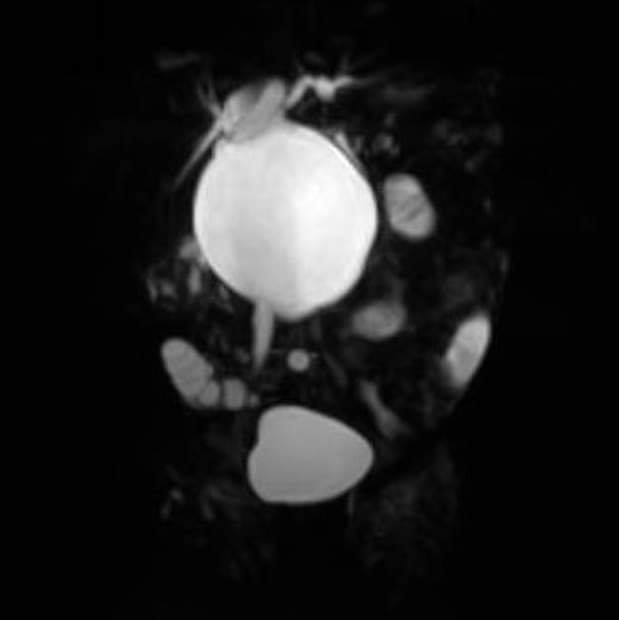

Cụ thể, 2 bé gái mới chỉ 50 và 57 ngày tuổi, phải nhập viện BV Nhi đồng Thành phố vì vàng da kéo dài sau sinh và người nhà sờ thấy khối ở vùng bụng của bé. Tại BV, các bé được chẩn đoán là nang ống mật chủ với kích thước nang rất lớn, với kích thước lần lượt là 5x3cm và 6x5cm.

Khi nội soi vào ổ bụng, Phẫu thuật viên (PTV) quan sát được ở cả 2 trường hợp nang ống mật chủ rất to, trong qua trình mổ cắt nang, trong nang có nhiều cặn bùn làm bít tắc đường mật, gây ra tình trạng vàng da niêm của bé.